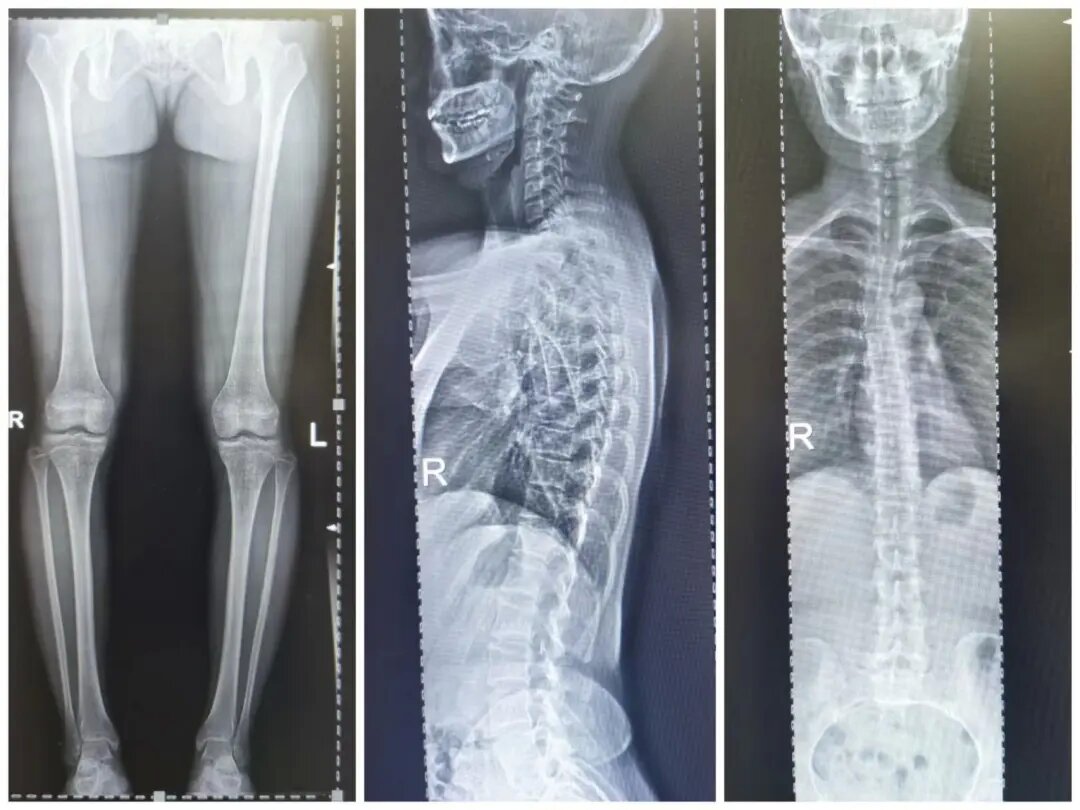

四、脊柱全長攝影及雙下肢全長攝影

對脊柱側彎、髖關節(jié)置換、膝關節(jié)置換給予全面、直觀的影像資料。